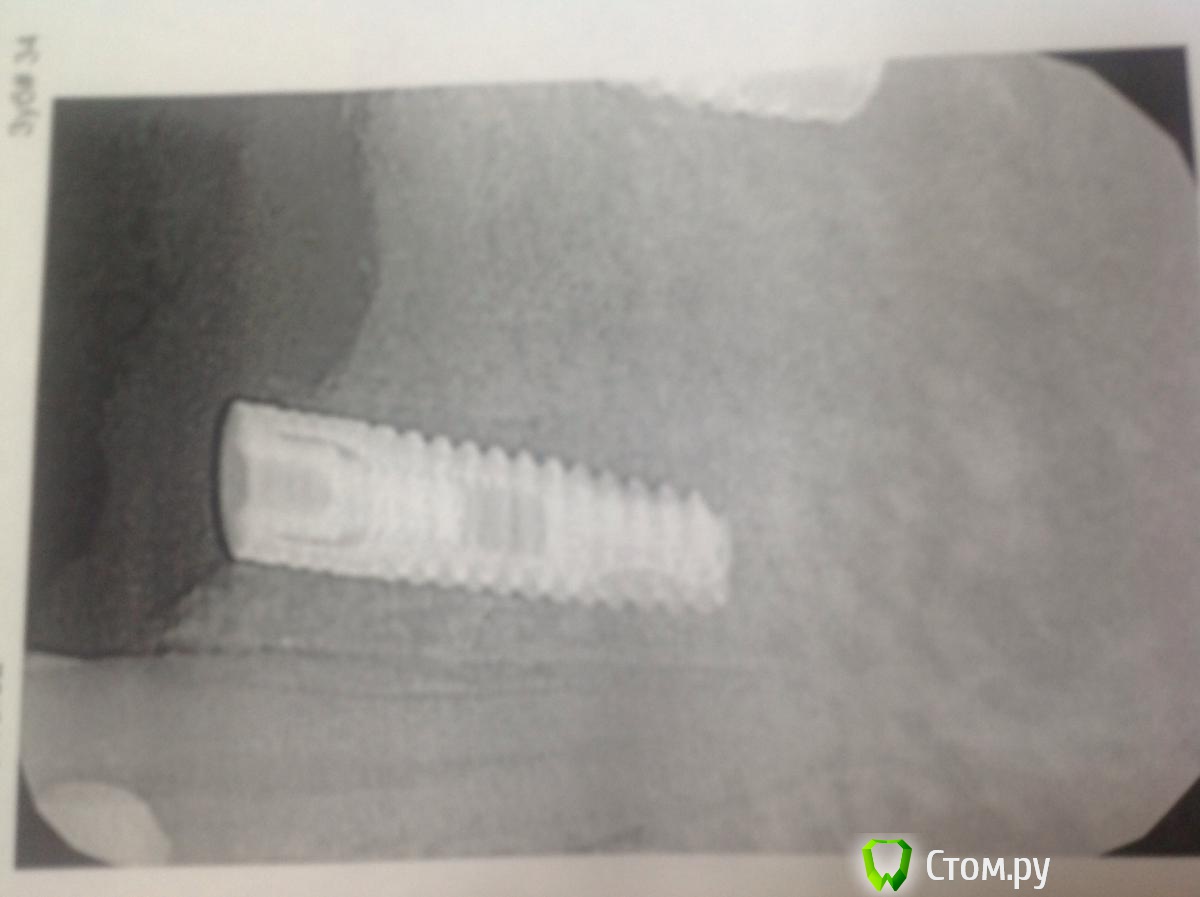

bullbull Опубликовано 20 ноября, 2013 Поделиться Опубликовано 20 ноября, 2013 Вот это имплантат по касательной! На первых двух фото 2011 год (винт установлен 2008-2009). На последнем фото пара недель назад перед удалением зуба. В лунке пальпируется верхушка винта. Удалять железо не хочет, так как ничего не беспокоит. Ссылка на комментарий